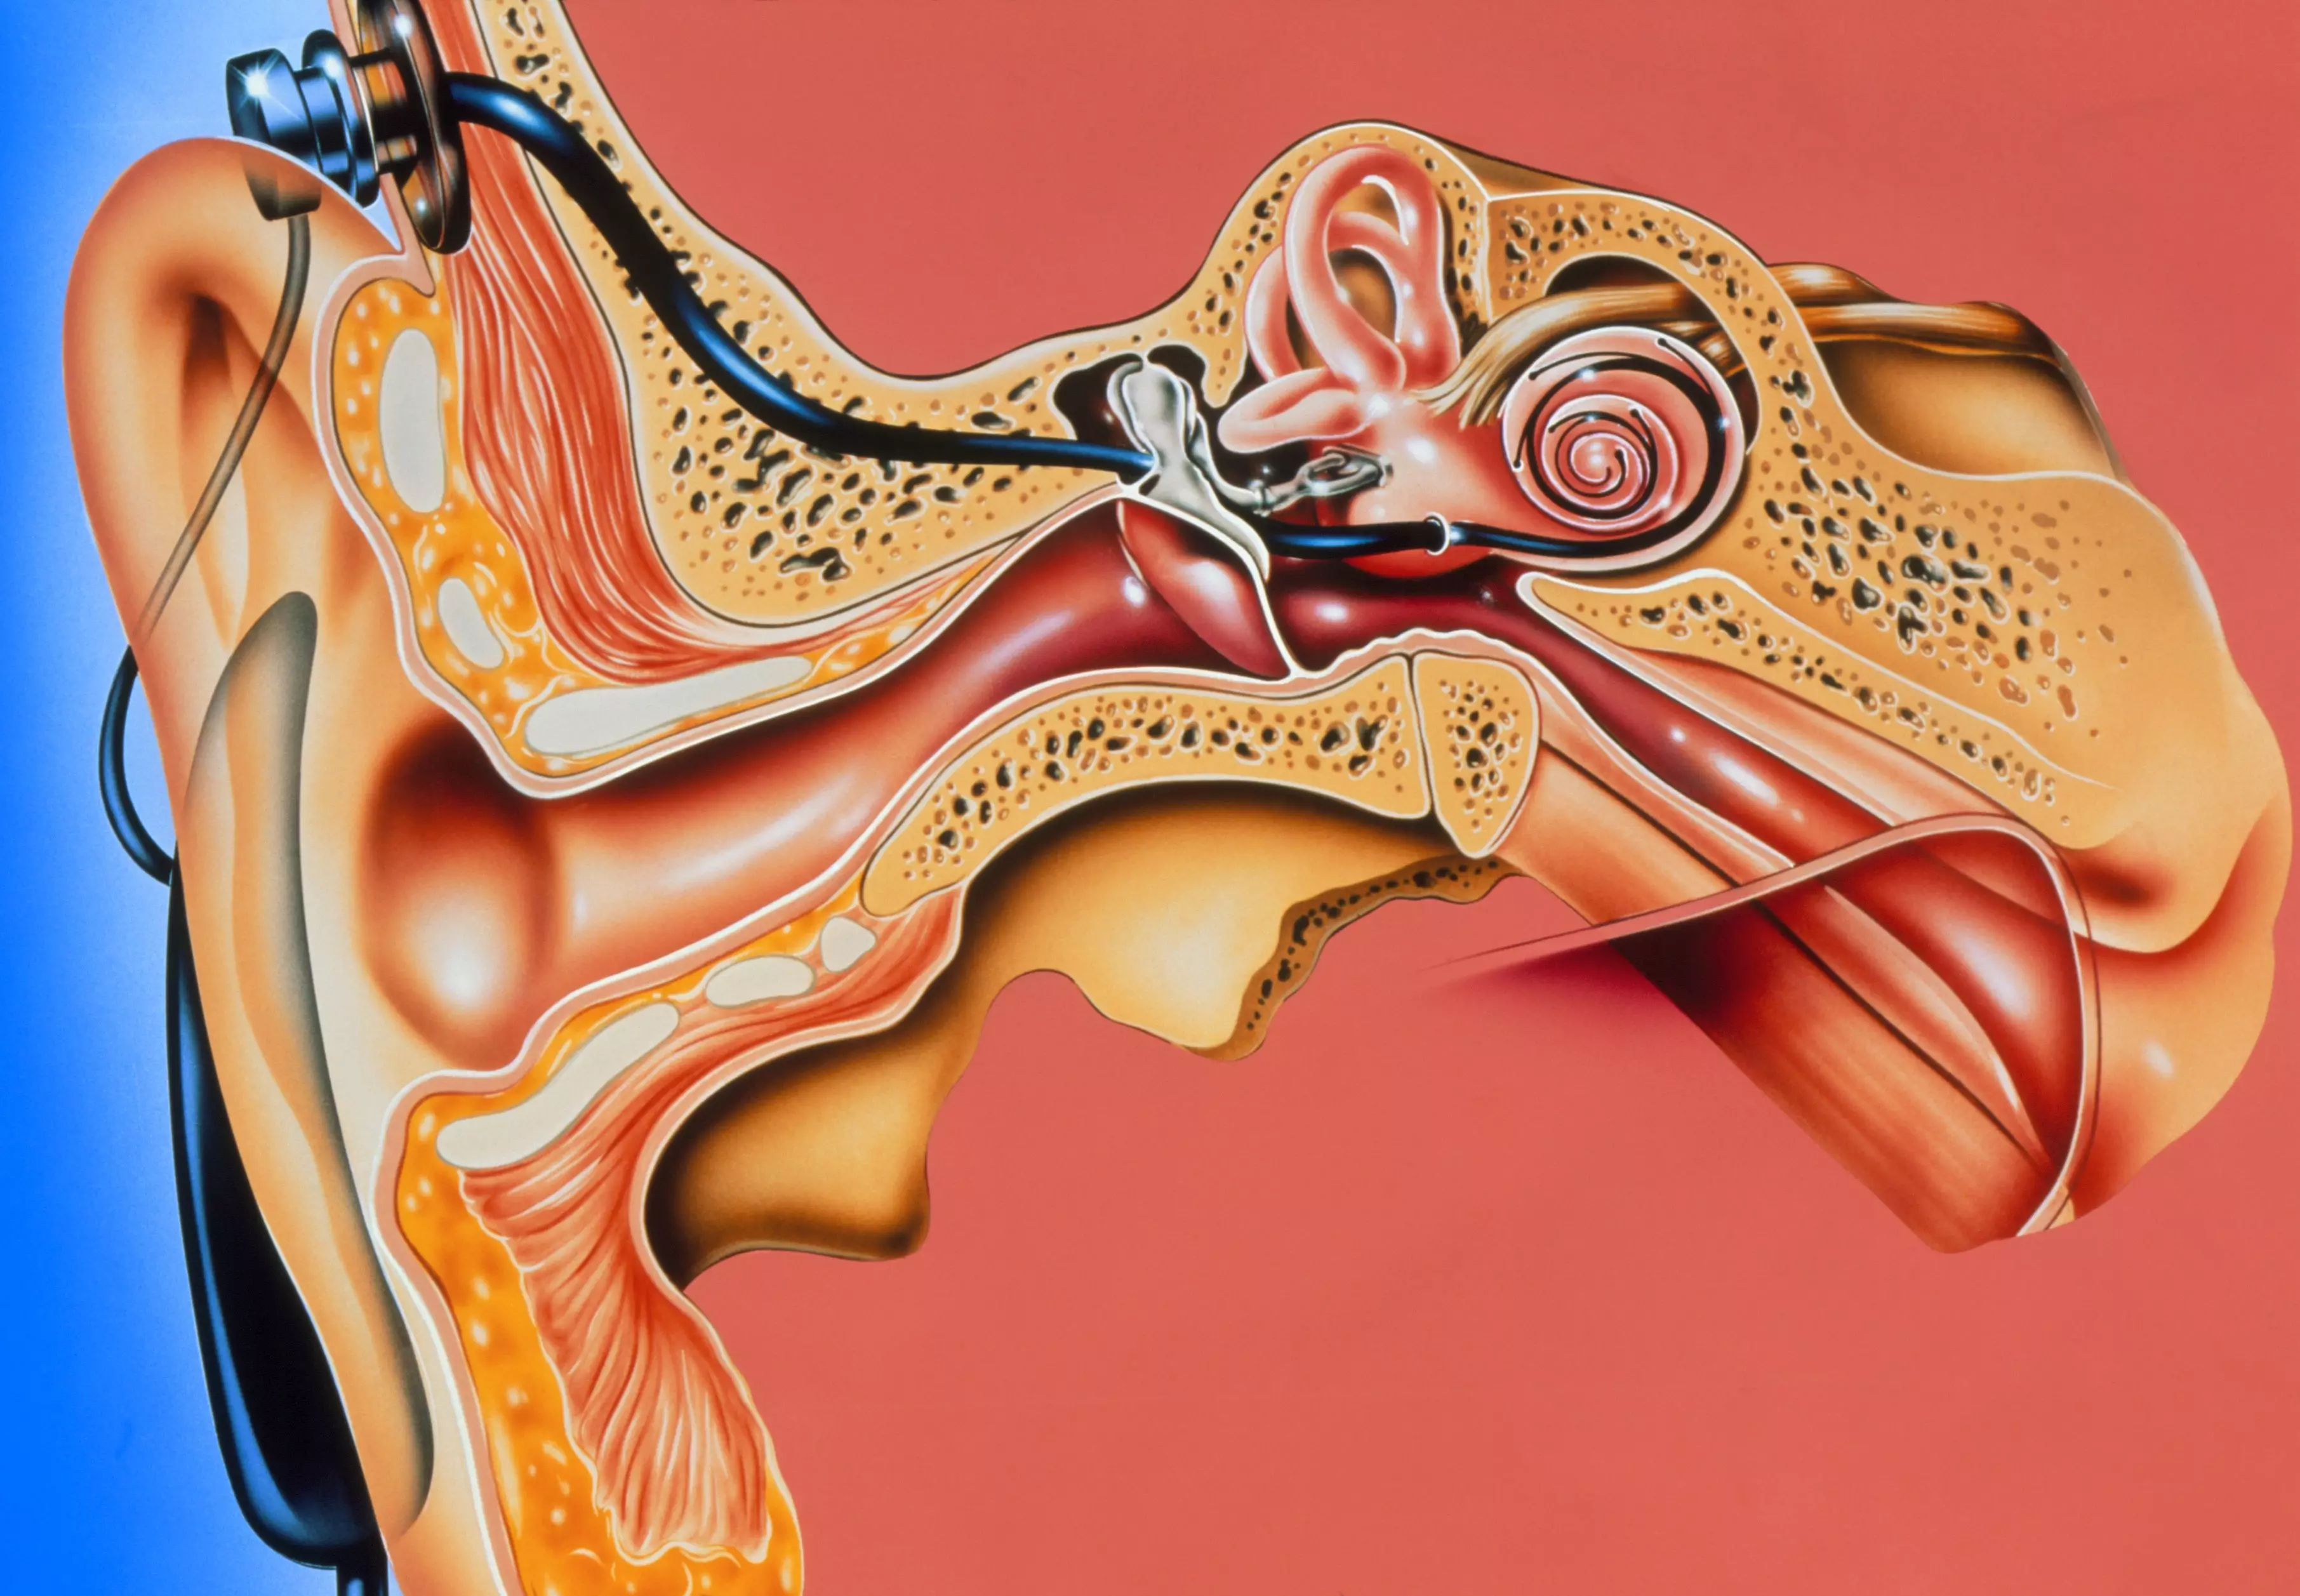

Современные слуховые аппараты при сенсоневральной тугоухости